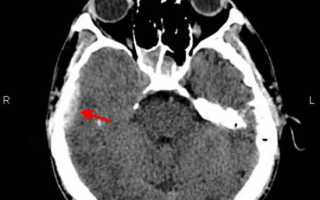

- Томография. Более точные данные об объеме и месте расположения гематомы, а также о других внутричерепных повреждениях, может дать КТ головного мозга. Изоденсивная и малая по размеру эпидуральная гематома визуализируется при помощи МРТ головного мозга. МРТ также применяется для дифференциации эпи- и субдуральных гематом, для оценки состояния базальных структур и ствола мозга.

КТ головного мозга. Эпидуральная гематома в височной области справа

При КТ выявляют линзовидное гиперплотностное объёмное образование, прилежащее к костям свода черепа. Чувствительность КТ — 100%, специфичность — 84% (в остальных 16% эпидуральная гематома может быть похожа на субдуральную). Перелом височной кости на краниограммах выявляют только у 60% больных.